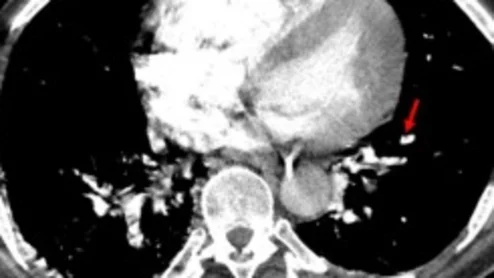

liver cancer

The completion of the first treatment represents a "significant milestone" for patients with liver cancer, the IR who led the procedure says.